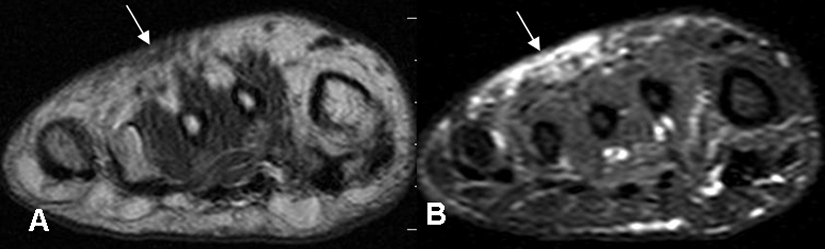

Fig 61. Pie diabético. Celulitis.

A: RM coronal en T1 y B: RM coronal en STIR. Edema de tejidos blandos en el dorso del pie, por celulitis. No hay compromiso óseo.